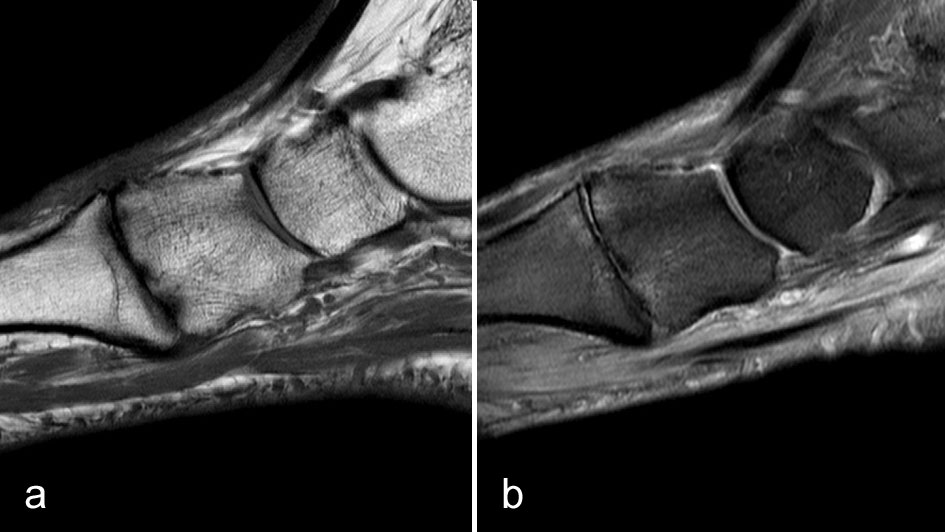

Aus obiger Auflistung der zu erwartenden Pathologien kann auf die sinnvolle Untersuchungstechnik bei der MRT geschlossen werden: Fettsupprimierte wassergewichtete Sequenzen (meist PD FS) in mindestens 2 Ebenen sowie eine T1-gewichtete Sequenz sind eine gute Basis für das Untersuchungsprotokoll, das dann je nach Fragestellung oder Befund ergänzt werden muss. Dies wird anhand der folgenden Fallbeispiele aufgezeigt.

Wenn Stressreaktionen- und frakturen Folge einer offensichtlichen Überlastung sind, ist die Diagnose in aller Regel klinisch und anamnestisch zu stellen. Die MRT dient eher der Unterscheidung zwischen reiner Stressreaktion und bereits eingetretener Fraktur (Abb. 1).

Bei inadäquater Besserung unter Entlastung kann der Ausschluß einer chronischen Stressreaktion oder einer sich entwickelnden Pseudarthrose ein Grund für eine MRT Untersuchung sein (Abb. 2).